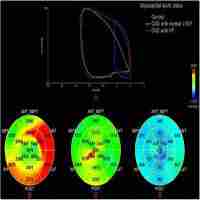

| Abstract | Cardiac systolic dysfunction was potentially found in adult patients with end-stage renal disease (ESRD) who have preserved left ventricular ejection fraction (EF%). In children with ESRD, little data are available on early changes in myocardial function. This study aimed to detect the early changes in myocardial mechanics in pediatric patients with ESRD using speckle tracking echocardiography (STE).Methods:Thirty ESRD children receiving hemodialysis (HD) and30 age-matched controls were prospectively studied. Patients underwent echocardiographic studies before and after HD. Left ventricular longitudinal strain (LS), circumferential strain (CS), and radial strain (RS) myocardial deformation parameters (strain, strain rate) were evaluated by STE.Results:The LS was significantly reduced in pre-HD and post-HD patients compared with controls (P = .000). Controls showed the highest global longitudinal strain. The RS measurements did not differ significantly among the studied groups except for the inferior segment that is significantly reduced after HD compared with controls (P < .05). The CS was significantly reduced in pre-HD and post-HD patients compared with controls at the lateral and posterior segments (P = .035 and P = .013, respectively).Conclusion:Speckle-tracking echocardiography might detect early changes in myocardial mechanics in children with ESRD with preserved EF%. |